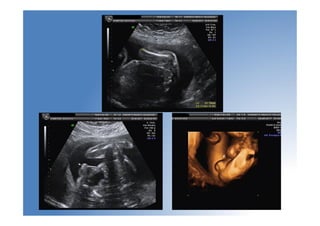

Anomalías sist. músculoesquelético

• Baja frecuencia

• Lo más importante: determinar su letalidad

• Displasia esquelética no letal más frecuente:

acondroplasia heterocigota ( se Dx en 3º T)

• Signo de alarma: Fémur corto (p<5 para EG, <

2DE)

• La mayoría de los LF cortos aislados son

constitucionales

• Displasia: LF < 4 DE. Sino: controles seriados

• Polihidramnios: signo de mal prónóstico